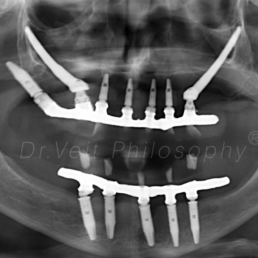

Arte de reabilitar os casos “impossíveis”. Pacientes que buscam a reabilitação oral podem conquistar um belo sorriso com segurança, mais conforto e tranquilidade com o uso do Implante Zigomático. A técnica possui o diferencial de realizar a implantação no osso zigomático e é indicada para casos de perda óssea maxilar avançada.